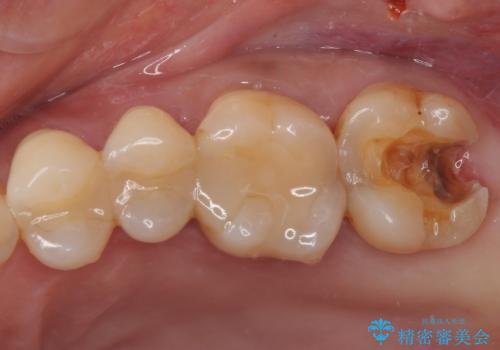

- 奥歯がかけてしまい、しみるようになったとのことで来院された患者様です。

上顎奥の粘膜に近い部分で、つめものの下には大きく虫歯が広がっていました。

虫歯をしっかりと取り除き、ゴールドインレーにて修復することとしました。